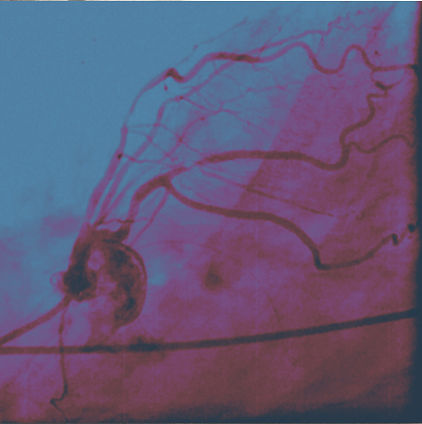

As with HIV, the successful treatment of SARS-CoV-2 requires a multi drug regimen to stop both the attachment and replication of the virus, AND the InflammoThrombotic Response (ITR) to the virus.